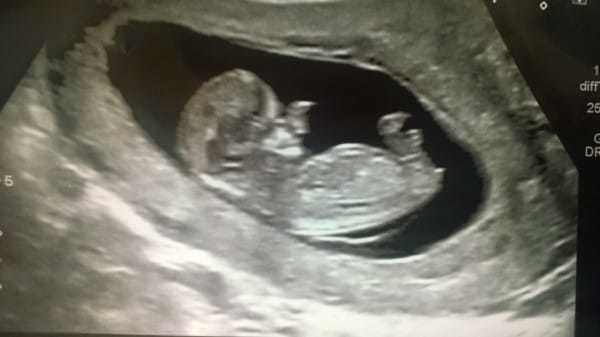

That year, his mother, Amy Poole, received shocking news during her second pregnancy. During the ultrasound, the doctor noticed something unusual on the baby’s face. Throughout the 20 weeks of her pregnancy, the doctor found that Amy’s son had uncontrolled soft tissue growth around his nose. Amy knew her son wouldn’t be like other children, but the reality was far more devastating than she imagined.

Ollie was born with a condition called “encephalocele.” A fracture in his skull caused his brain to develop through a hole in his head and nose. His nose was deformed, large, and almost covered half his face. This condition is extremely rare; only 1 in 10,000 children in the US are born with this defect each year.